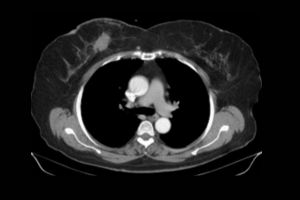

A CT scan bilateral sacroiliac joint (also known as bilateral sacroiliac joint imaging) is a medical procedure that uses X-ray technology to create cross-sectional images of the sacroiliac joints. By offering high-resolution images, this procedure allows healthcare providers to closely examine the bones, cartilage, and surrounding tissues of the SI joints. The use of contrast dye can help make the images clearer, allowing doctors to find conditions like fractures, arthritis, and swelling more easily. It is often suggested when X-rays or MRIs are not enough to identify specific issues with the sacroiliac joints.

- Contrast Injection (if required): If contrast is used to enhance the images, a technician will inject the contrast dye into your veins.